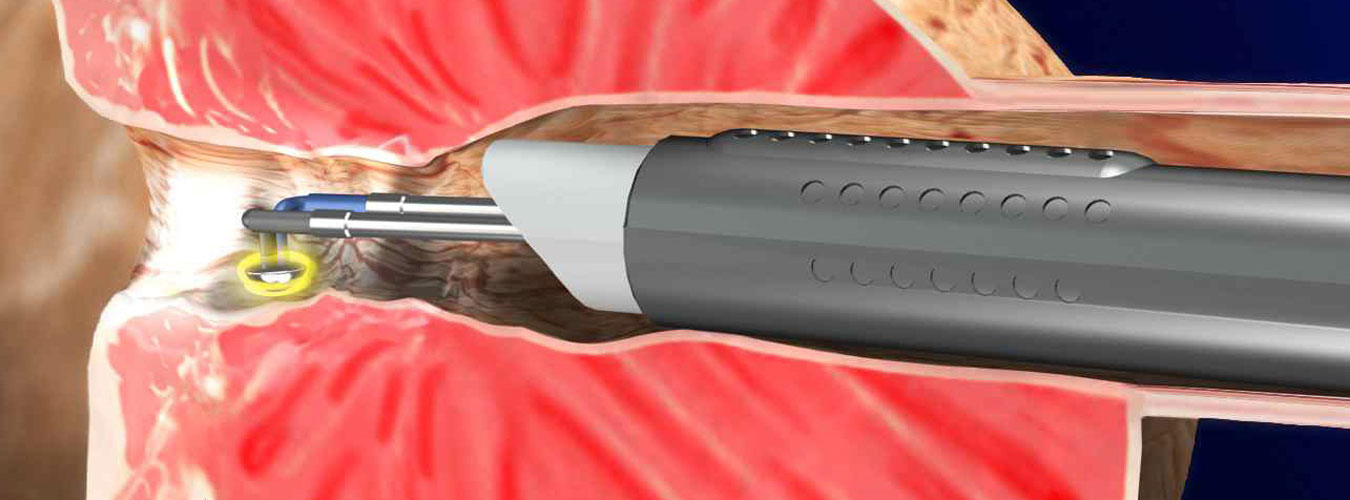

Καμία τεχνική δεν είναι πανάκια, διαβεβαιώνω με την εμπειρία και τη γνώση 30 και πλέον χρόνων. Συνεχίζω ο ίδιος να εκπαιδεύομαι σε νέες τεχνικές, καθώς π.χ η ρομποτική χειρουργική υπερέχει σε συγκεκριμένη κατηγορία ασθενών. Ωστόσο, επιλέγω π.χ την παλιά, «ανοιχτή τομή» για μια επέμβαση 7΄ λεπτών αντί για μιας λαπαροσκοπικής, διάρκειας μιάμισης ώρας με ό,τι αυτό συνεπάγεται για τη νάρκωση και το κόστος εκ μέρους του ασθενούς. «Εκσυγχρονίζομαι» με ιστοσελίδα διότι η εποχή το απαιτεί, αλλά παραμένω «κλασικός» στη θεωρία, ότι δεν κάνει η τεχνική τη διαφορά, αλλά η γνώση, με την προϋπόθεση βεβαίως, ότι γνωρίζει ο ιατρός όλες τις τεχνικές και δεν κατευθύνει. Για άλλες περιπτώσεις είναι εντυπωσιακά τα αποτελέσματα της λαπαροσκοπικής χειρουργικής και για άλλες η διαδερμική ή η ενδοσκοπική προσέγγιση. Ειδικά στη λιθίαση, η ενδοσκοπική ουρητηροσκόπηση, μας «έλυσε τα χέρια» για την πλειοψηφία των περιπτώσεων αφαίρεσης λίθου και ειδικότερα για τα παιδιά και τους ασθενεις με μεταμοσχευθέντες νεφρούς .